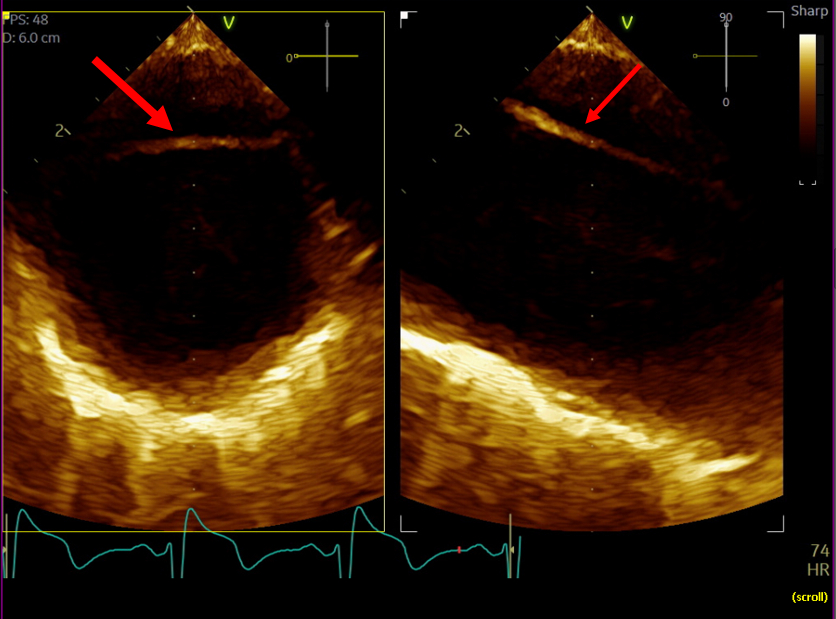

A 42-year-old male with history of a Type A aortic dissection with surgical repair 3 years earlier, resistant hypertension, hyperlipidemia, and prior tobacco use, presented for chest pain radiating to his back. Physical exam was notable for a 2/6 systolic murmur, most prominent at the aortic position. Initial vitals were significant for hypertension, with a blood pressure of 164/105 mmHg. Laboratory testing showed troponin elevated to 30 ng/L (reference < 15 ng/L), with a stable 3-hour trend. EKG showed normal sinus rhythm with left axis deviation and left ventricular hypertrophy. A CT angiography (CTA) dissection protocol showed a dissection flap distal to the left subclavian artery, extending into the abdominal aorta, consistent with a Stanford Type B aortic dissection (TBAD). The patient was managed with beta blockers and vasodilators to maintain systolic blood pressure under 120 mmHg and heart rate under 60 beats per minute. Following symptom resolution, a repeat thoracic CTA revealed a 2.5 cm sac near the origin of the right main coronary artery, representing a pseudoaneurysm not seen prior. Subsequent cardiac CTA confirmed this pseudoaneurysm outpouching secondary to degeneration of the TBAD. The patient underwent successful pseudoaneurysm repair with anastomosis construction and Dacron patch placement.

While the patient’s initial presentation and imaging studies, consistent with a TBAD, suggested conservative management, repeat imaging was imperative and changed the therapeutic plan despite the resolution of his symptoms. Current ACC/AHA guidelines recommend medical management for uncomplicated Type B dissections with close monitoring; however, aneurysmal progression mandates timely surgical intervention to mitigate rupture risk. This case highlights the importance of serial imaging in patients with TBADs to detect evolving complications such as APA formation, which may initially be occult but carry high mortality risk if left untreated.